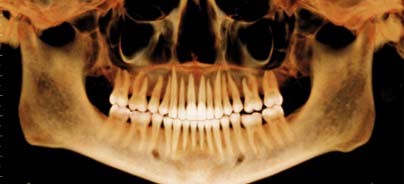

Der Einsatz digitaler Volumentomografie eröffnet ohne Frage ein breites Spektrum an diagnostischen Möglichkeiten (Abb. 1 und 2). Um hierbei jedoch betriebswirtschaftlich sinnvoll agieren zu können, müssen einige wichtige Aspekte berücksichtigt und im täglichen Umgang mit DVTs entsprechend umgesetzt werden. So stellen neben dem großen Investitionsvolumen insbesondere der Datenschutz sowie die Langzeitarchivierung den Praktiker vor große Probleme.